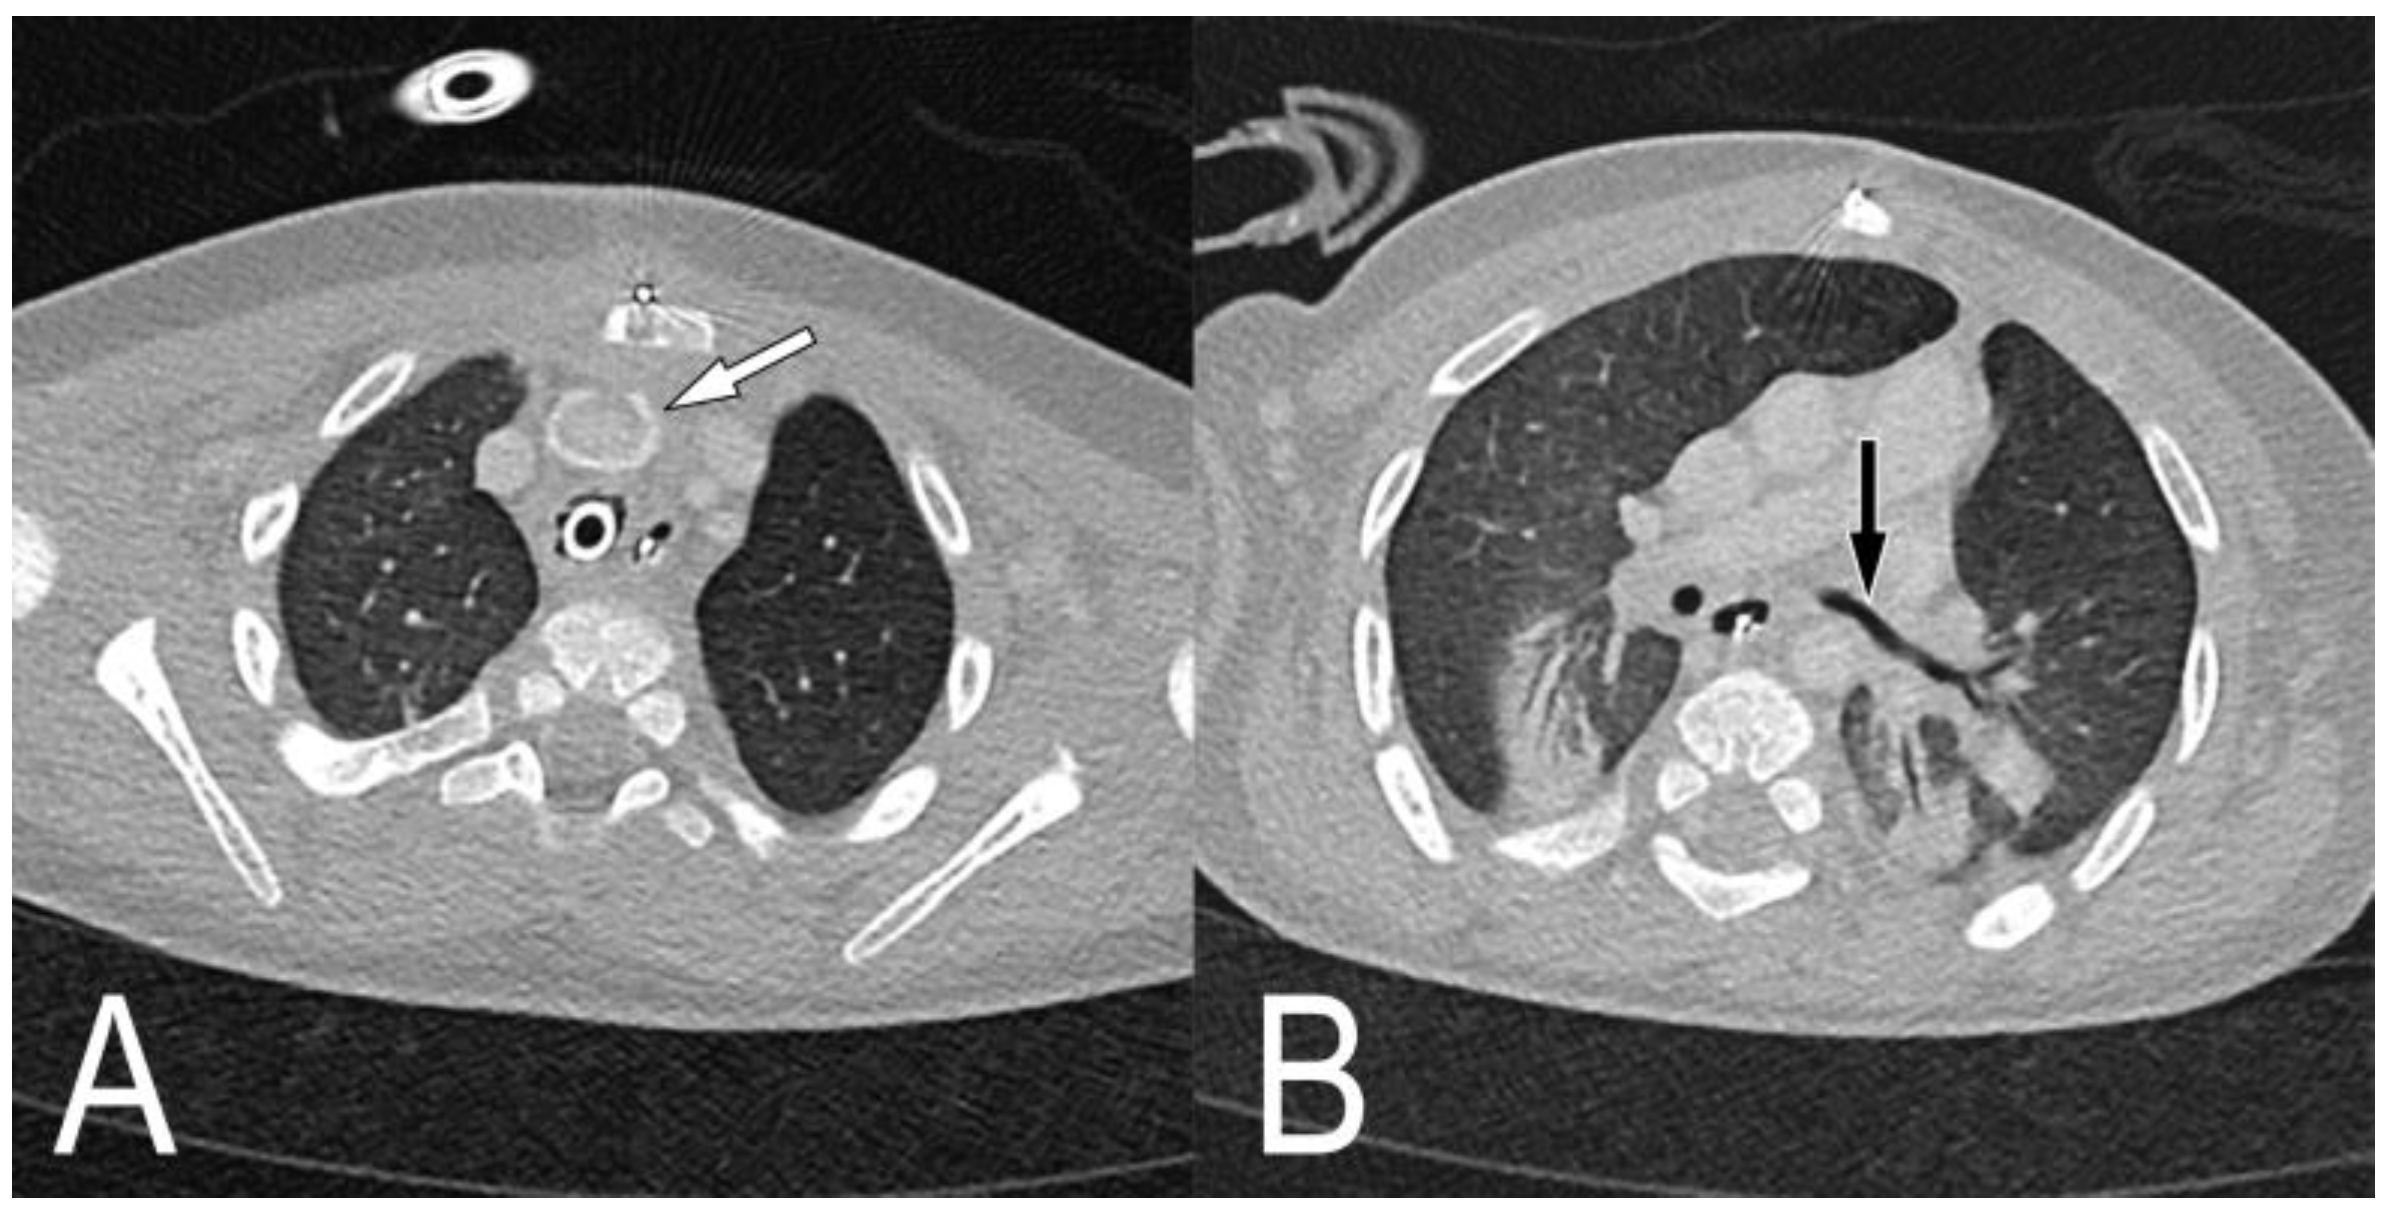

2.1. Case 1

2.2. Case 2